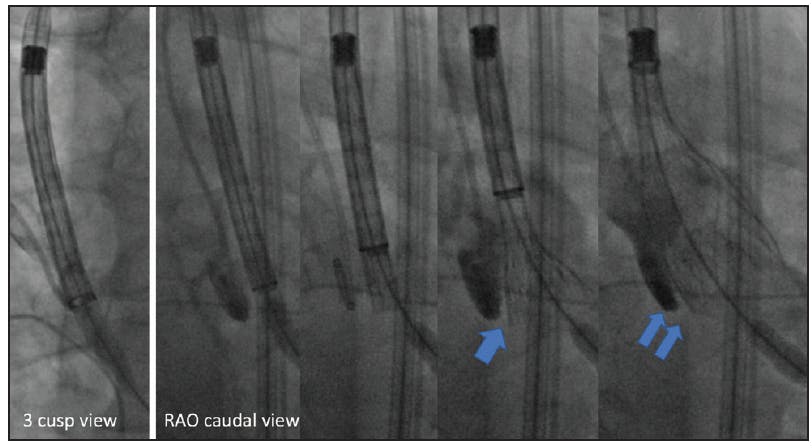

Figure 3. In the three-cusp annular plane view the valve is not in plane. However, in the RAO caudal views, both the valve and the device are in plane. The sheath is withdrawn, exposing the valve level with the base of the pigtail. Further withdrawal, flaring of the valve with its base 3 mm below the annular plane, is then followed by deployment to 80% (double arrow) under rapid ventricular pacing, and then subsequent release.